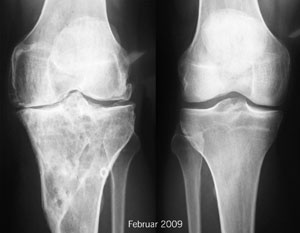

In Zermatt trete ich morgen früh Skitag Nummer 58 dieses Winters an. Gut! Es gibt auch wieder neue Röntgenbilder - auch wenn ich lieber auch links die Qualität des rechten Knies hätte, bin ich ganz zufrieden... kaum Veränderungen.

Röntgenbilder Februar 2009 - Klicken für grössere Fassung